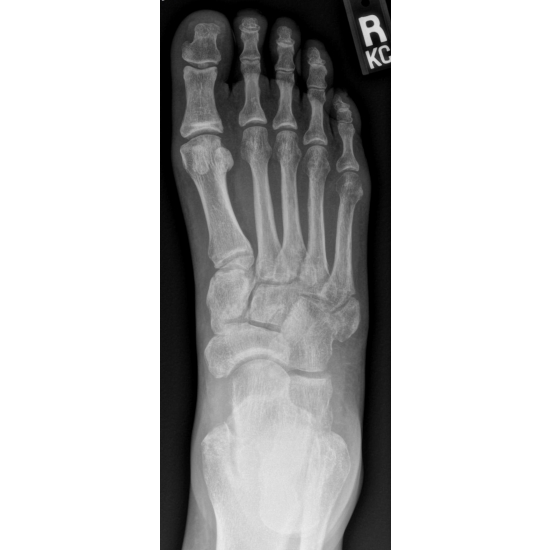

She continued with protected weight bearing in a walking boot and was later placed in a non-weight bearing cast for 4 weeks because of increasing diastasis of her fracture pieces. Case Photo #3 Case Photo #4